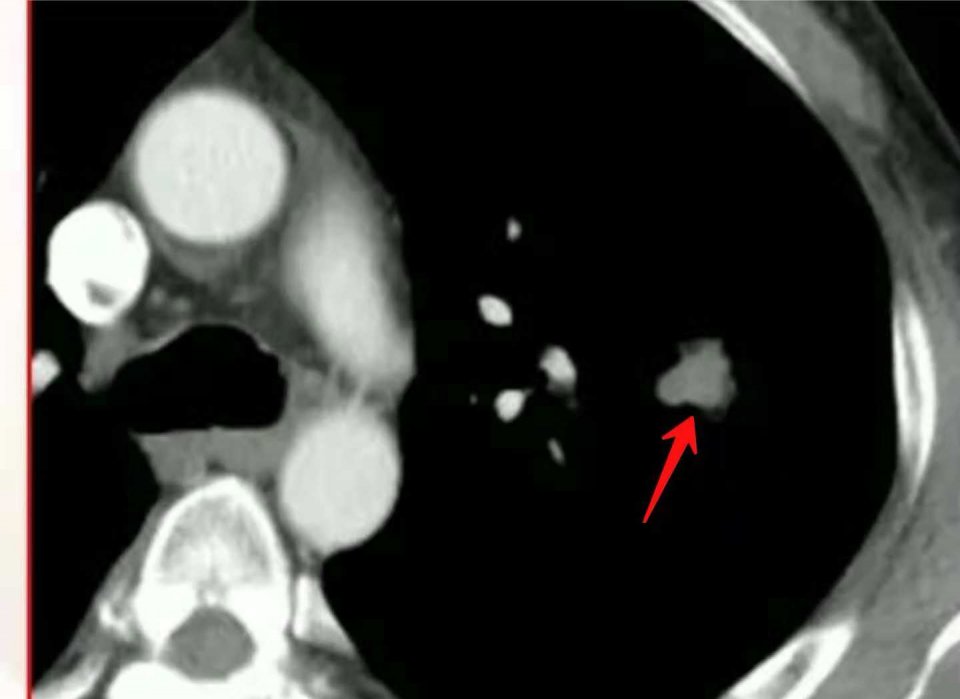

2.中年男性,左侧小细胞肺癌,局部淋巴结转移:

这位病人经过放化疗为主的综合治疗,目前已经生存5年多了。